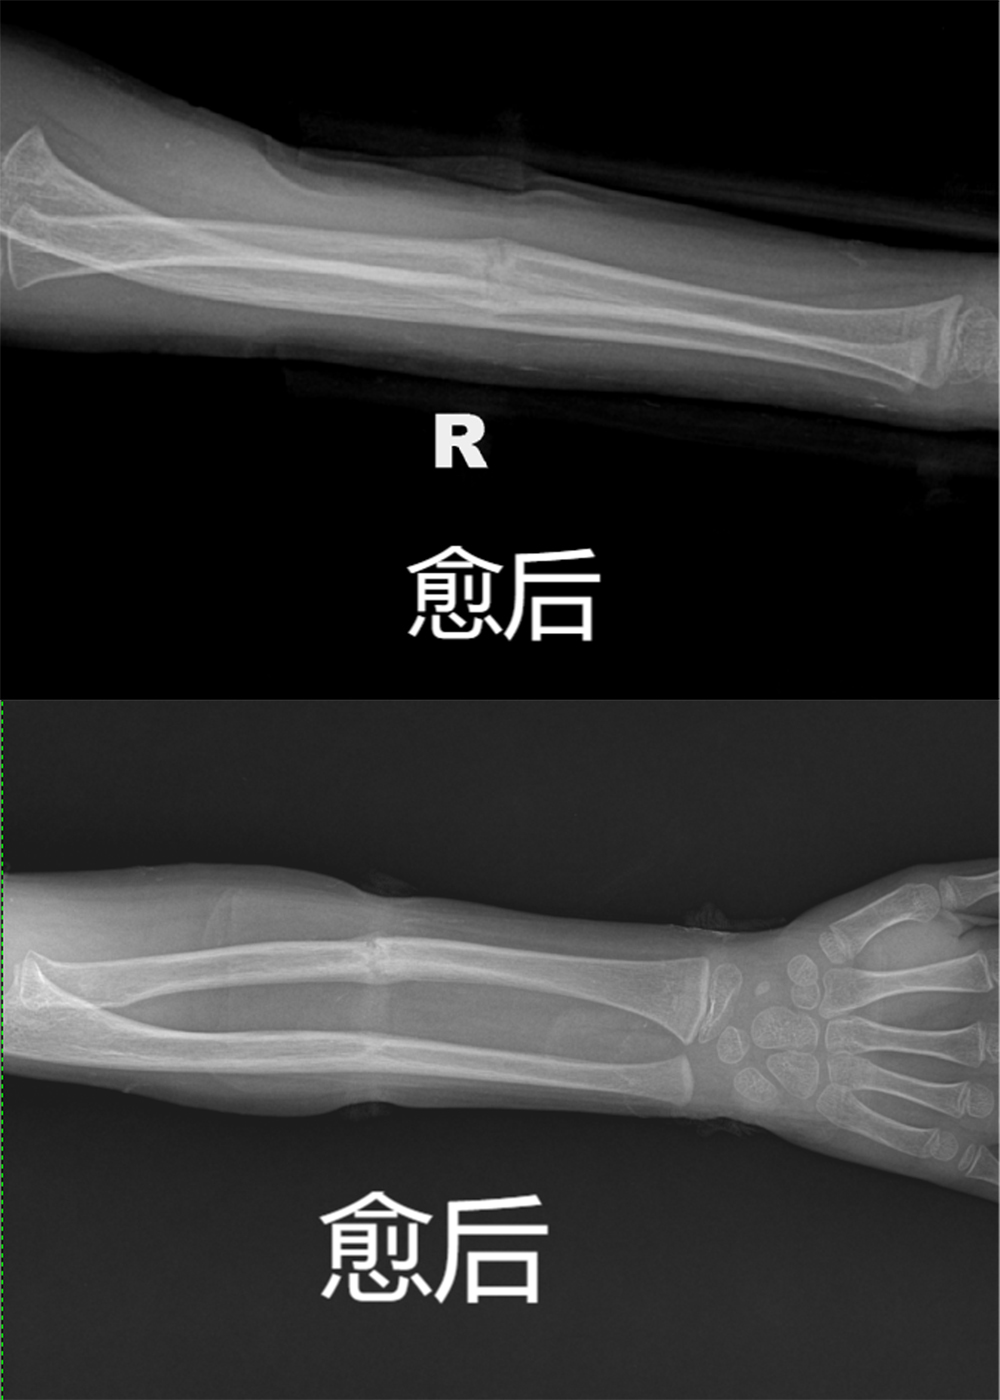

患者2个月后复查愈后良好,去除外固定后可以正常活动

愈后.jpg